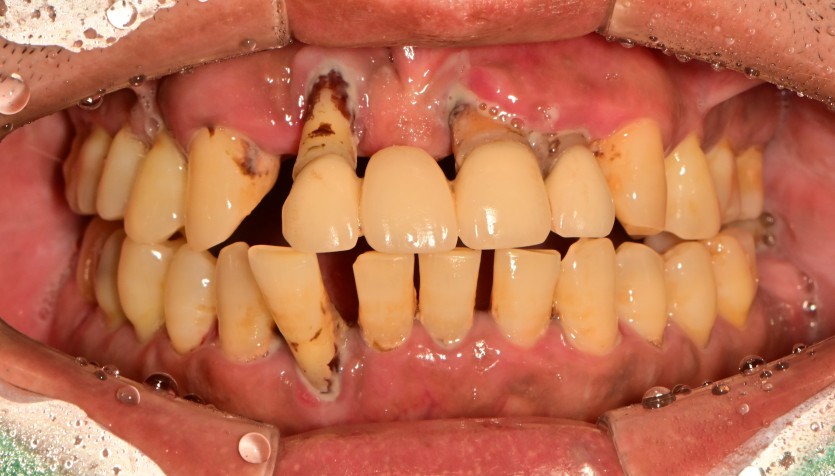

만 40세 상악 전체 임플란트 증례(하악 일부)

상악 전체 임플란트 증례입니다.(하악 일부)

14개의 임플란트로 완성하였습니다.